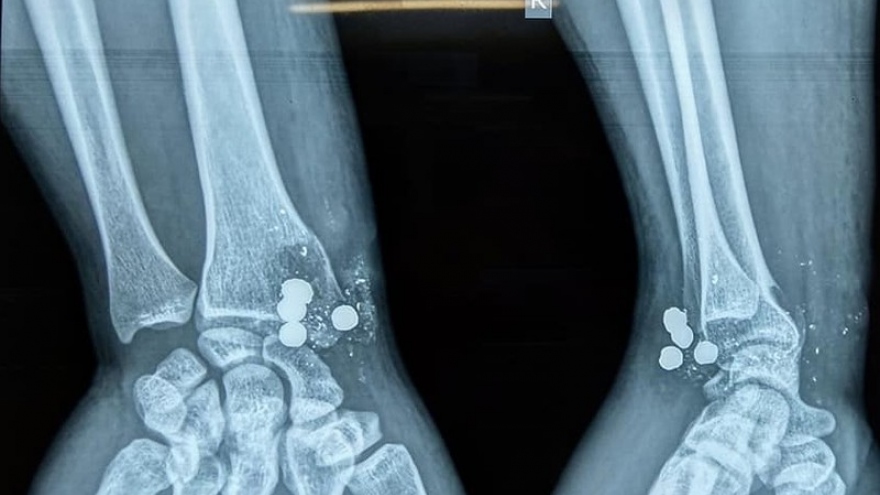

Súng kíp phát nổ bắn 5 viên đạn vào cổ tay người đàn ông

VOV.VN - Thấy nhà bạn có khẩu súng kíp, anh Th lấy xuống xem thì bất ngờ súng phát nổ, 5 viên đạn cắm thẳng vào cổ tay người này.